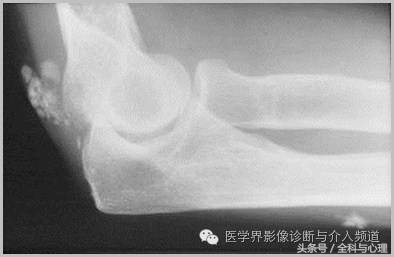

五、滑膜软骨瘤病

1°少见,病灶数量多,大小均匀,相邻关节正常。

2°多见,病灶数量少,大小不一,多伴有退行性骨关节病。

软组织钙化与骨化,软组织钙化和骨质增生 滑膜骨软骨瘤病 1°

软组织钙化与骨化,软组织钙化和骨质增生 滑膜骨软骨瘤病 2°

软组织钙化与骨化,软组织钙化和骨质增生 滑膜骨软骨瘤病